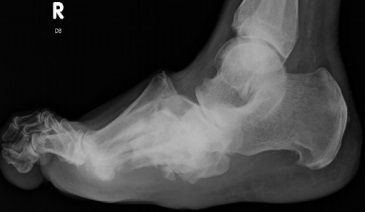

| What is this called? What does an anterior break indicate? What does a posterior break indicate? | Cyma Line/Midtarsal joint. Anterior break = pronated foot type Posterior break = supinated foot type |

| What is this? What foot type is this visible in? | Sinus tarsi/bullet hole sign. Pes cavo-varus |

| What is this? What foot type is this visible in? | Double talar dome sign. Pes cavo-varus |